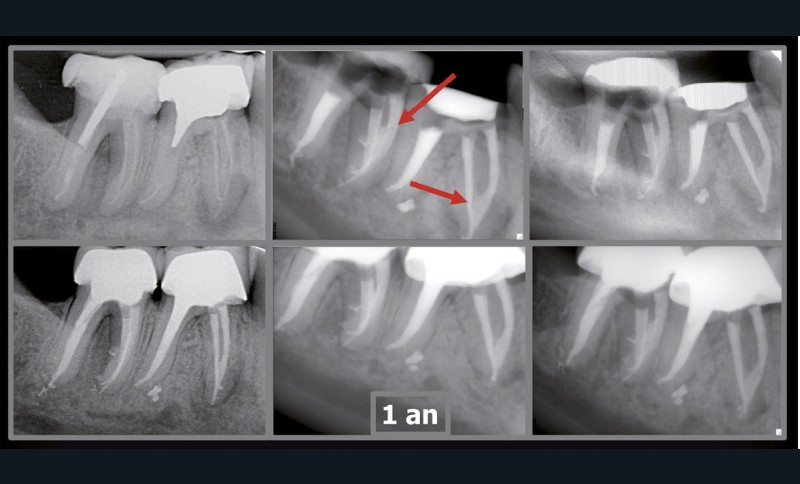

Endal, en 2011, montrait également, en utilisant le micro CT Scanner, l’insuffisance de nettoyage des isthmes inter-canalaires à nos techniques conventionnelles [19]. L’utilisation du laser Er:YAG devenait alors incontournable dans le nettoyage de ces isthmes et des zones non instrumentées (fig. 2 et 3).

Si l’étude de Peters [18] nous montre que l’instrumentation laisse 35 % du volume canalaire non instrumenté, Ricucci et Siqueira montrent que la préparation physico-chimique n’élimine que partiellement les tissus nécrotiques à l’entrée des canaux latéraux, des isthmes et des ramifications apicales, en laissant des tissus enflammés et infectés, en association avec des lésions apicales [29] (fig. 4 et 5).